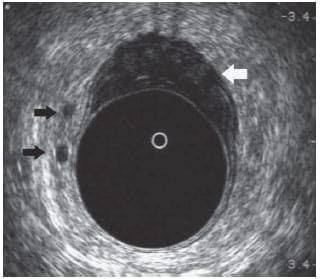

Permite valorar lesiones que pueden estar en el interior del recto, como pólipos o tumores, o en sus paredes, como lesiones de los esfínteres anales y musculatura del suelo pélvico, prolapso rectal, etc., o por fuera de la pared del ano y recto, como inflamaciones (abscesos), fístulas, y otras patologías.